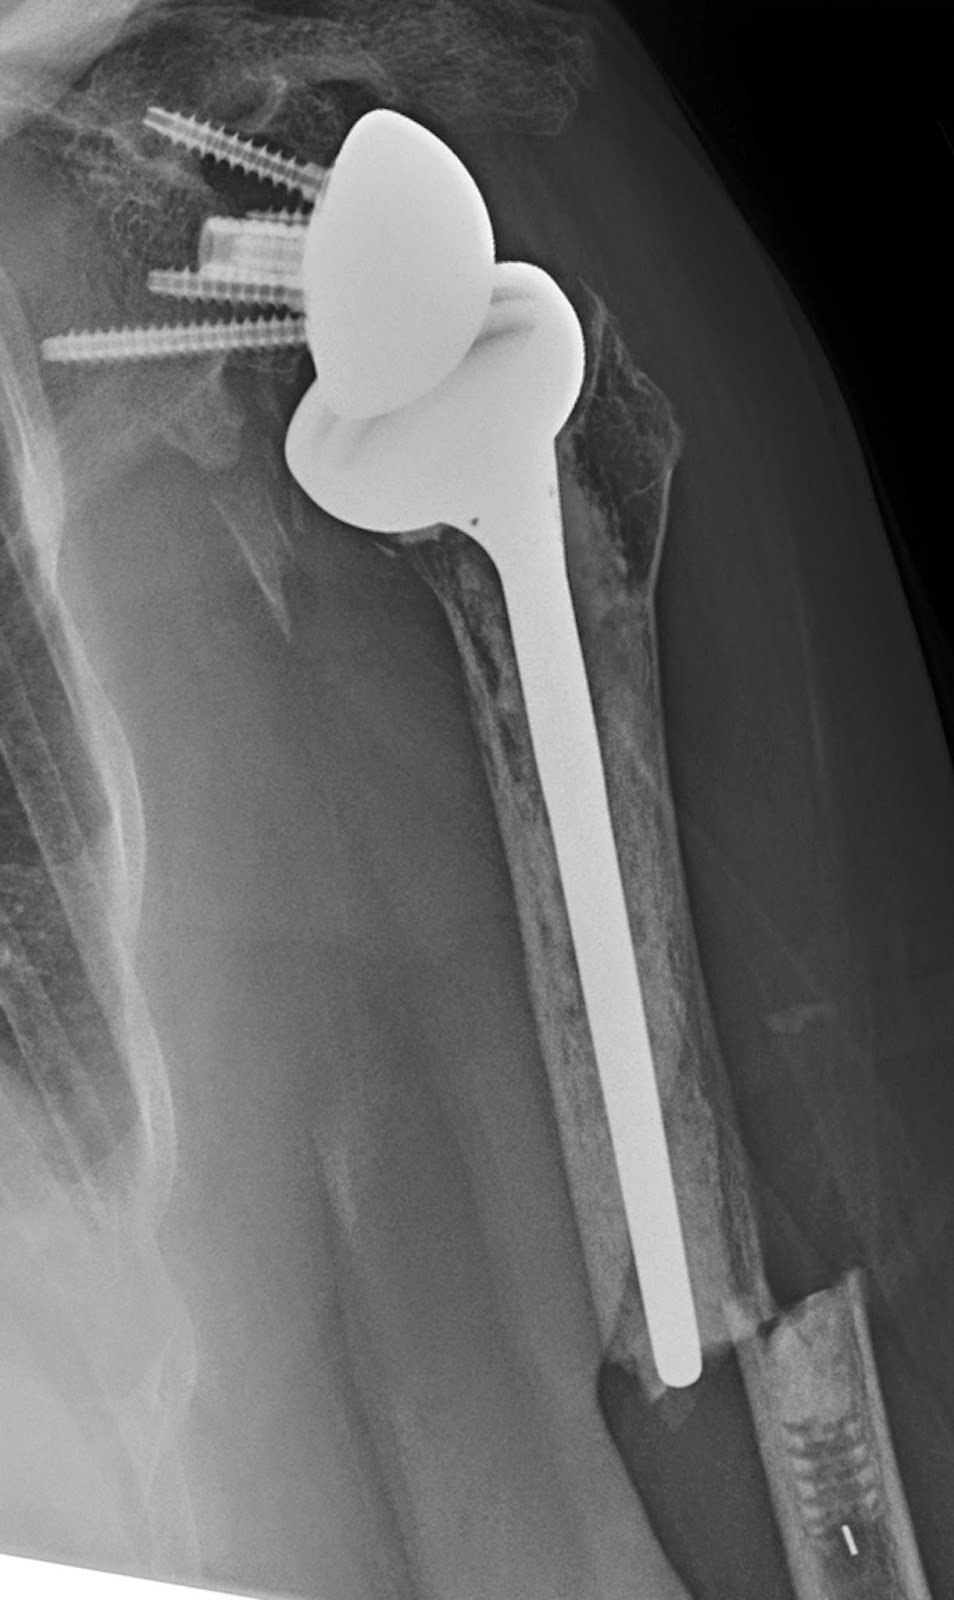

Prosthesis shoulder replacement image This picture illustrates prosthesis shoulder replacement.

Less pain after surgery 2, which may. General endotracheal intubation was achieved without complication. Shoulder replacement, also known as arthroplasty, is a type of surgery that relieves pain and helps a joint work the way it should. 1 one of today's shoulder replacement techniques may be an option for you if other more conservative options have not helped you regain your range of motion and your strength, and reduce your pain. A total shoulder replacement completely replaces the ball and socket components of the shoulder.

Backward shoulder replacement is a type of shoulder replacement fashionable which the median ball and socket relationship of glenohumeral joint is transposed, creating a many stable joint with a fixed fulcrum. The reverse® shoulder prosthetic device is a twist made of all-metal and polyethylene. The longstanding or anatomic berm replacement involves reconstructing the shoulder sharing in a style similar to the normal anatomy. It prevents smooth motion of the shoulder, humeral head and the socket in which it fits. How more you can anticipate to pay exterior of pocket for shoulder replacement, including what people paid. Shoulder replacement is A surgical procedure stylish which all OR part of the glenohumeral joint is replaced by letter a prosthetic implant.

In shoulder replacement surgery, the shoulder joint, is replaced by an artificial joint prosthesis. The primary objective of this operation, is the reduction of pain in the affected shoulder.

The big differences between a reverse prosthesis and a standard shoulder replacement is that in a reverse prosthesis, the ball is placed on the socket side of the joint. This is opposite where it is located in nature, or “reverse” of what you would expect.